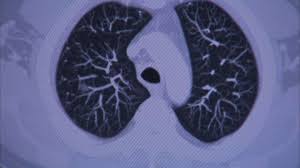

Lung Cancer Signs And Symptoms Mayo : Https Www Mayoclinicproceedings Org Article S0025 6196 11 64785 X Pdf - Signs and symptoms of lymphoma may include:. Chronic, hacking, raspy coughing, sometimes with mucus that has blood in it. Because there are very few nerve endings in the lungs, a tumor could grow without causing pain or discomfort. As the cancer develops, these symptoms may become more severe or intense. Sometimes, metastatic disease may not cause any symptoms, though about 30 percent to 40 percent of people with lung cancer will have symptoms of metastasis. Many people with lung cancer don't have symptoms until the disease is in its later stages.

Lung cancer usually has no symptoms in its early stages. Metastatic lung cancer symptoms depend on the part of the body to which the cancer has spread, as well as the size and location. The inset shows three swollen lymph nodes below the lower jaw. Lung cancer remains the leading cause of cancer deaths in the u.s., among both men and women. The symptoms of lung cancer in women are sometimes different than in men, largely because both sexes tend to get different types of lung cancer.

Lung Cancer Diagnosis And Treatment Mayo Clinic from www.mayoclinic.org Weight loss is also almost universal, and it occurs even when people are eating a diet with adequate calories. But catching physical warning signs and traces of cancer early on increases your likelihood of survival. Signs and symptoms of small cell lung cancer, anemia in people with cancer. international journal of cancer : According to the american cancer association, approximately 234,030 new cases of lung cancer are being diagnosed every year and about 154,050 deaths occur due to lung cancer. Typical symptoms, which usually appear only when the disease is advanced, include a persistent cough, shortness of breath, chest pain, coughing up blood and hoarseness. Lung cancer symptoms also resemble those of many other conditions, making it hard to discern the cause. Because lung cancer develops in the lungs, as you'd probably expect, its most common symptoms involve the lungs. Shoulder discomfort that is related to lung cancer may worsen at night, be present while resting or occur without impacting range of motion.

The symptoms of lung cancer in women are sometimes different than in men, largely because both sexes tend to get different types of lung cancer. Shanda blackmon outlines some of the different types of lung cancer as well as signs and symptoms. Lung cancer that has spread to the bones may cause pain at the sites of the affected bone. Throat cancer is a general term that applies to cancer that develops in the throat (pharyngeal cancer) or in the voice box (laryngeal cancer). If it has spread to the brain it may cause a number of neurological symptoms and headaches. According to the american cancer association, approximately 234,030 new cases of lung cancer are being diagnosed every year and about 154,050 deaths occur due to lung cancer. A persistent cough that doesn't go away and gets worse over time; But catching physical warning signs and traces of cancer early on increases your likelihood of survival. Lung cancer remains the leading cause of cancer deaths in the u.s., among both men and women. Stanifer explains that, in rare cases of lung cancer, patients may experience hypercalcemia — heightened levels of calcium in the body — which can manifest in physical symptoms such as chronic. Though most throat cancers involve the same types of cells, specific terms are used to differentiate the part of the throat where cancer originated. Typical symptoms, which usually appear only when the disease is advanced, include a persistent cough, shortness of breath, chest pain, coughing up blood and hoarseness. Signs and symptoms of lung cancer typically occur when the disease is advanced.